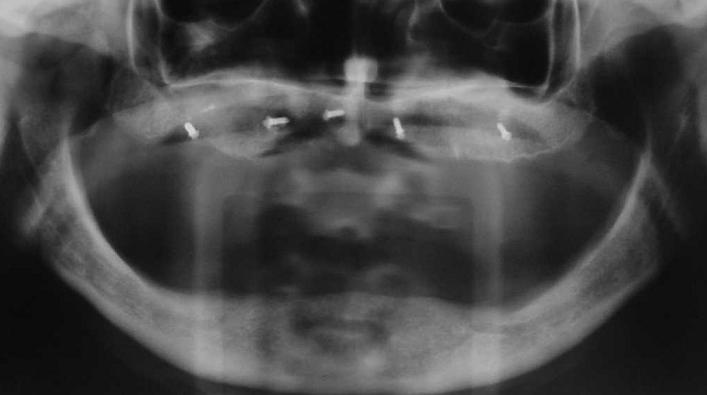

Paciente Desdentado com enxerto ósseo na Maxila

IMPLANTES SUPERIORES INSTALADOS APÓS O ENXERTO ÓSSEO E IMPLANTES INFERIORES